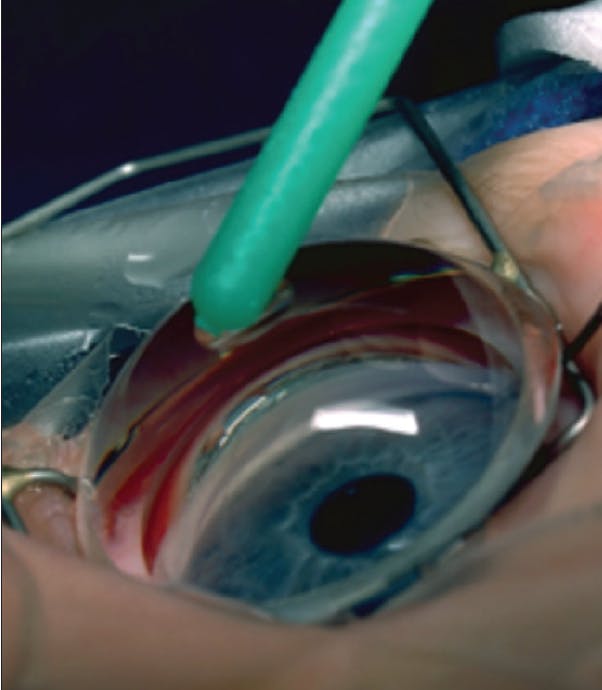

The existing hypothesis for how angle surgery works in children is that incising an abnormal trabecular meshwork (or Barkan membrane) reestablishes flow to Schlemm canal and that the downstream collector system is unaffected by primary disease. This hypothesis has remained unquestioned since Barkan’s time. An advantage of my practicing in the same area for 3 decades is that I have gotten to observe many of my pediatric patients into adulthood. Figure 2 is a photograph I took 28 years ago during an ab externo Harms trabeculotomy in an infant. I treated only the superior 120º, but, during follow-up, except for some scattered peripheral anterior synechiae superiorly, the patient’s angle was normal in appearance. This case and similar cases have made me question whether, in actuality, angle incision restarts the arrested development (eg, cleavage of tissue planes) of angle structures underlying primary congenital glaucoma and other developmental glaucomas.

Figure 2. A photograph taken nearly 3 decades ago during an ab externo trabeculotomy on an infant eye. Only the superior 120º was treated, but, at a recent follow-up appointment, the patient’s angle was normal in appearance.